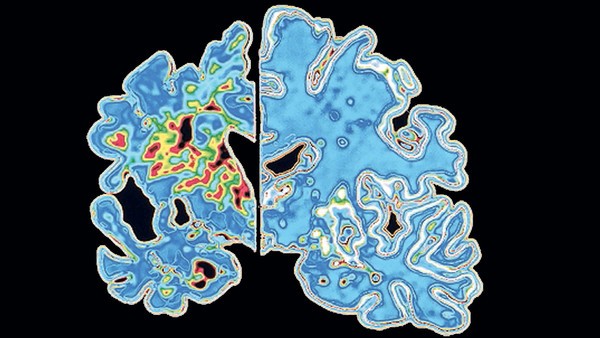

به گفته برگزار کنندگان کنفرانس بین‌المللی انجمن آلزایمر در آمریکا، در نشست این کنفرانس در روز چهارشنه، ٣١ تیر (٢٢ ژوئیه)، شرکت دارویی الی لیلی، که یک شرکت آمریکایی است، نتیجه آزمایش‌های کلینیکی شیوه درمانی با استفاده از دارویی را اعلام کرد که نشان می‌دهد می‌توان سرعت تحلیل سلول‌های مغزی مبتلایان به آلزایمر را به طرز قابل توجهی کاهش داد و مانع از تشدید بیماری شد.

به گزارش نوروسافاری به نقل از بی بی سی هلث، تاکنون درمان آلزایمر عمدتا متوجه کاهش آثار و عوارض بیماری و در نتیجه، ایجاد شرایط بهتر برای بیمار بوده است اما پژوهشگران شرکت الی لیلی گفته‌اند که شیوه جدید، که به آن سولانزوماب Sulanezumab نام داده‌اند بیماری را کمابیش در مراحل اولیه متوقف می‌کند یا دست کم از شدت گرفتن آن به طور موثر جلوگیری به عمل می‌آورد.

آزمایش‌های اولیه دارو در سال ۲۰۱۲ تاثیر مشخصی را نشان نداد اما زمانی که پژوهشگران به یافته‌های قبلی حاصل از این آزمایش‌ها نگاه کردند، متوجه شدند که ظاهرا در مورد افراد مبتلا به عوارض ملایم تر آلزایمر موثر بوده است.

شیوه‌های درمانی رایج آلزایمر می‌کوشد به یاخته‌های مغزی کمک کند تا به شکل بهتری با هم ارتباط داشته باشند اما این شیوه‌ها مانع از ادامه روند بیماری نمی‌شود و به این ترتیب، با گذشت زمان و آسیب بیشتر به مغز، کارآیی این شیوه‌ها نیز کاهش می‌یابد.

در مقابل، گفته می شود که روش درمانی جدید به شکلی موثر عامل بیماری را هدف قرار می‌دهد و مانع از آن می‌شود که با سرعت هر چه بیشتر، به مغز آسیب برساند و بیماری را وخیم‌تر کند.